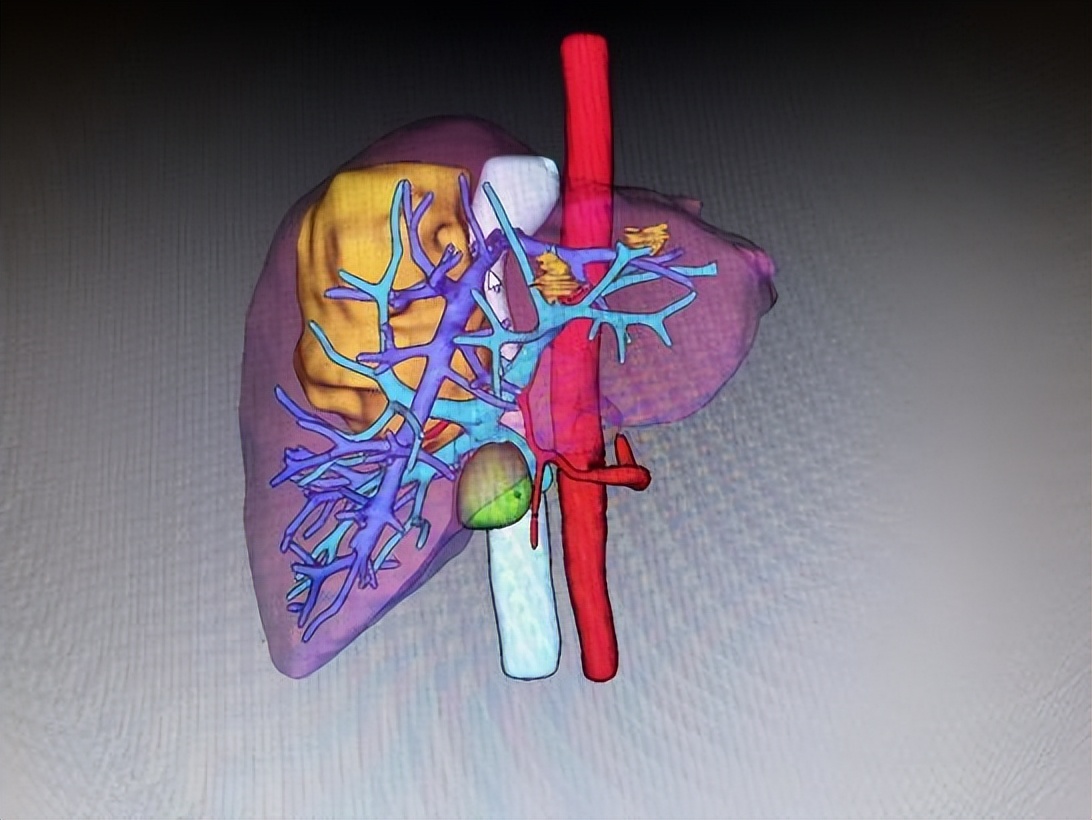

52岁的王女士一周前因腹痛并发双下肢水肿于当地医院检查发现肝脏上有一类椭圆形巨大肿瘤。在当地医生推荐下,来到哈医大一院肝脏外科就诊。入院后,陆朝阳教授团队,通过科学精密的术前检查和3D成像技术,明确肿瘤位于肝脏右后叶和尾状叶,如成年男性拳头大小,确诊为肝血管瘤,肿瘤体积巨大且位于肝脏S7段及尾状叶腔旁部并紧邻人体几条重要大血管(下腔静脉、右肝静脉、右侧门静脉),其中肿瘤后壁全程压迫整个肝后下腔静脉,右肝静脉被肿瘤头侧压扁血流流出受阻,肿瘤左侧位于肝脏尾状叶(腔旁部)曾一度被称为手术禁区,手术难度已是极大。但不仅如此,患者肝脏血管畸形,右后下肝静脉(多长一条右肝静脉)位于肿瘤足侧,将传统肝右后叶微创手术路径彻底封死,这导致想要将肿瘤安全地微创切除甚至开刀切除几乎不可能完成。

▲图1 术前肝脏CT、三维可视化提示肿瘤所在位置